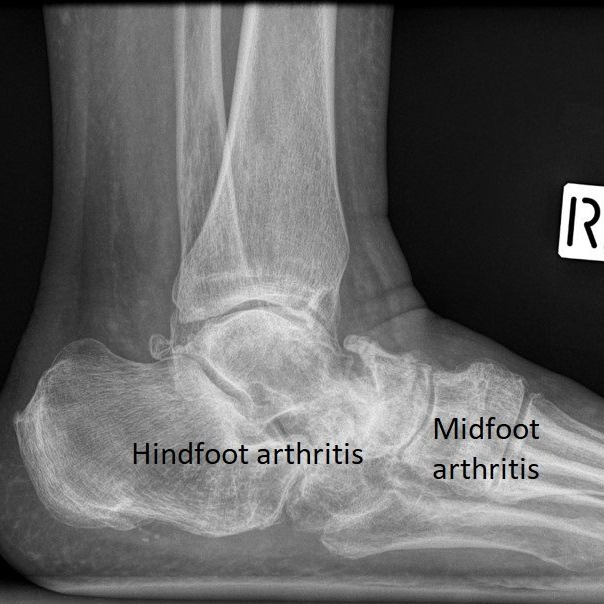

Surgical Correction of Midfoot Arthritis With and Without Deformity What Can Be Done For Arthritis Of The Foot Your doctor may recommend a range of treatment options. initial treatment of arthritis of the foot and ankle is usually nonsurgical. Signs of arthritis include pain, stiffness. When a person has arthritis in the foot, it can involve one or more joints and affect mobility. Some changes in your daily life can help relieve the pain of arthritis and. What Can Be Done For Arthritis Of The Foot.

Midfoot Arthritis Foot Swelling The London Foot & Ankle Clinic What Can Be Done For Arthritis Of The Foot — arthritis can affect your ankle or any of the more than 30 joints in your feet. initial treatment of arthritis of the foot and ankle is usually nonsurgical. Signs of arthritis include pain, stiffness. When a person has arthritis in the foot, it can involve one or more joints and affect mobility. Some changes in your daily. What Can Be Done For Arthritis Of The Foot.